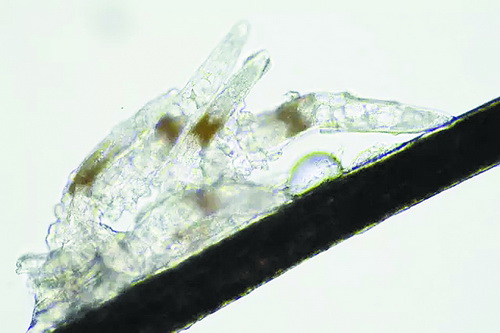

顯微鏡下長(zhǎng)在睫毛中的螨蟲(chóng)

冬天來(lái)了,氣溫降低,睫毛上的“隱形殺手”蠕形螨卻沒(méi)有要冬眠的意思。廈門大學(xué)附屬?gòu)B門眼科中心11月初開(kāi)設(shè)蠕蟲(chóng)性瞼緣炎門診以來(lái),每天來(lái)查螨的市民都特別多,短短一個(gè)多月,已有近千人在顯微鏡下見(jiàn)到長(zhǎng)期寄居在自己睫毛上,朝夕相處,卻素未謀面的蠕形螨。